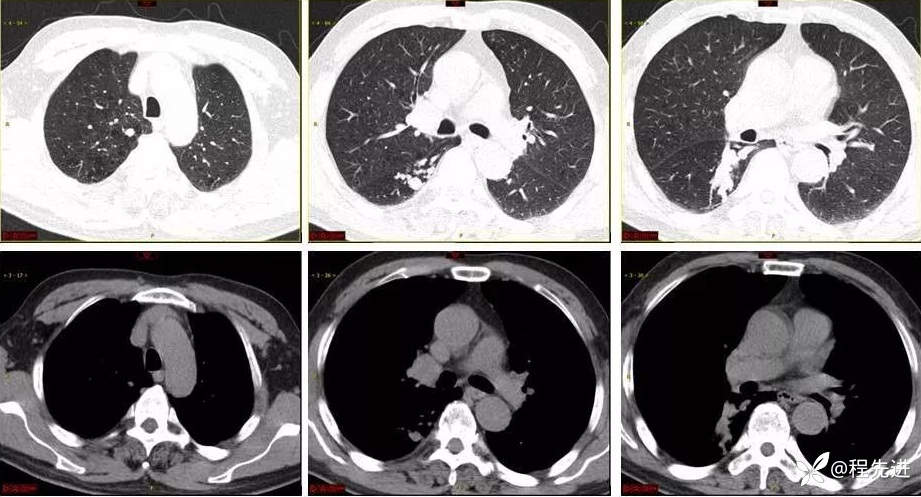

9月特别精彩病例|咳嗽伴咯血4月余,重点讨论胸部|结果已公布

患者性别:男

患者年龄:65岁

主诉:咳嗽伴咯血4月余

现病史:患者4月余前劳动后出现咳嗽,为阵发性干咳,以中午为主,后出现咯血,呈鲜红色,共5-6次,量最多时约50ml,约有3-4次。外院予以对症治疗(具体不详)后好转,1周前患者又出现咯血一次,约10ml。患者病程中无发热,时有胸闷,无胸痛,无呼吸困难,无盗汗,无恶心呕吐,无呕血黑便,食欲睡眠可,二便正常,体重无明显下降